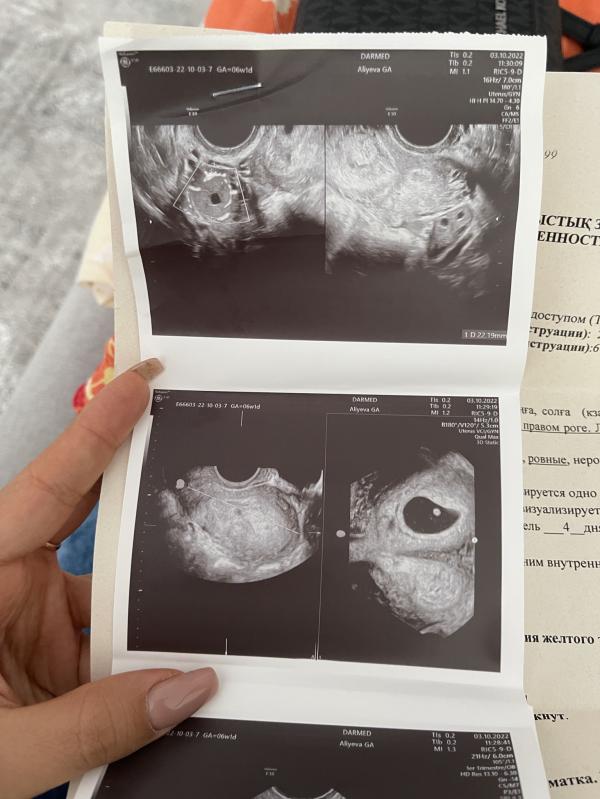

Забеременеть получилось сразу; страхов было очень много из-за двурогой матки и полного удвоения матки ( две матки).

На 8-й неделе появилось гематома, начала принимать дюфастон и магний. На 13 неделе из- за аномалии развития перевели в роддом на ЭКСПО.

Уже забыла на которой неделе гематомы на узи не было, если не ошибаюсь через несколько недель после первого скрининга. Из-за внутреннего волнения на УЗИ ходила стабильно раз в две недели. Слушала сердечко и расслаб...